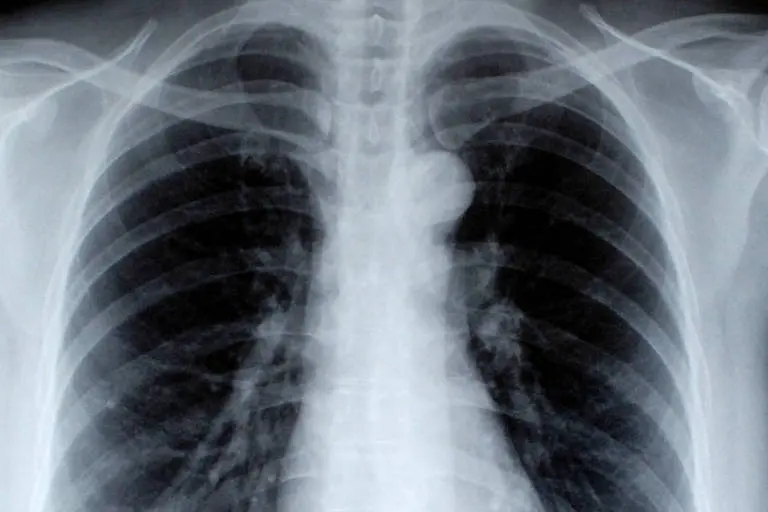

O câncer de pequenas células é o tipo mais agressivo no pulmão, embora não seja o mais comum.

No Brasil, incidência e mortalidade associadas à neoplasia pulmonar são consideradas altas.

A estimativa do Inca (Instituto Nacional de Câncer) é de que apenas em 2024 surjam mais de 32 mil casos novos de câncer de pulmão no país, sendo 18 mil entre homens e 14 mil entre mulheres. Em 2022, 29 mil mortes foram provocadas pela doença.